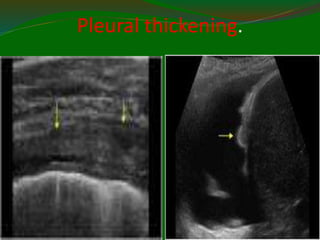

Pleural thickening.

11/21/2022